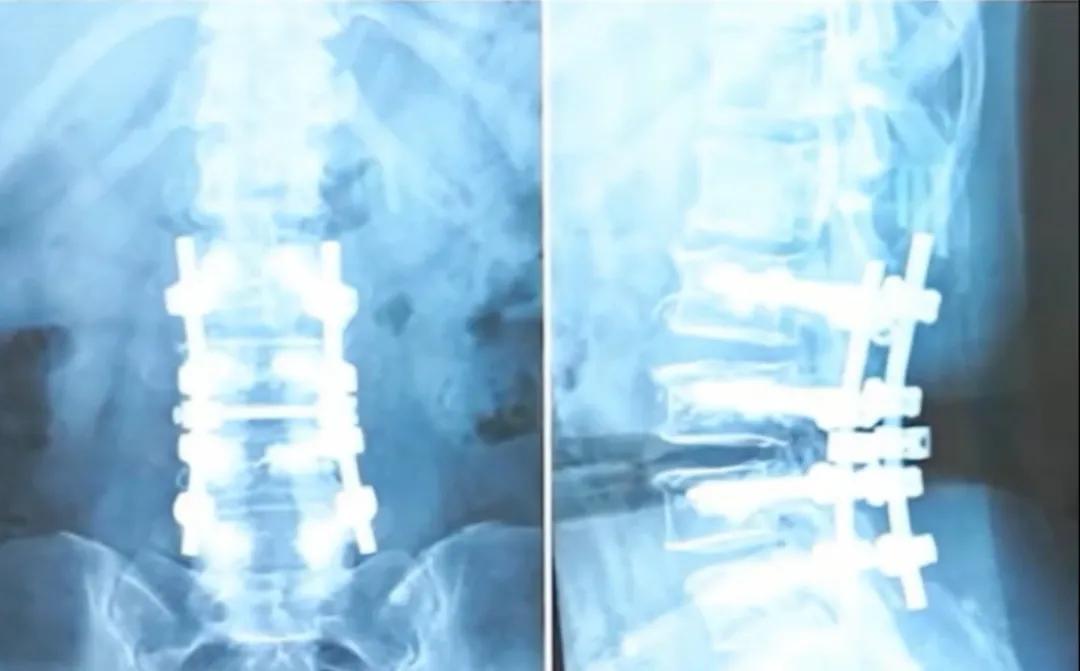

영상 속 50대 환우분처럼, 그녀는 심각한 척추관 협착증과 골다공증으로 수술 치료를 받았습니다. 척추의 안정성을 유지하기 위해 왕 주임은 그녀의 요추에 4쌍(총 8개)의 나사를 삽입하고 골 시멘트를 사용하여 추체를 강화했습니다. 이런 수술은 듣기에 '대대적인' 조치처럼 들릴 수 있지만, 놀랍게도 수술 후 그녀의 요추 유연성은 여전히 좋았으며, 심지어 두 손으로 바닥에 닿을 수 있었습니다.